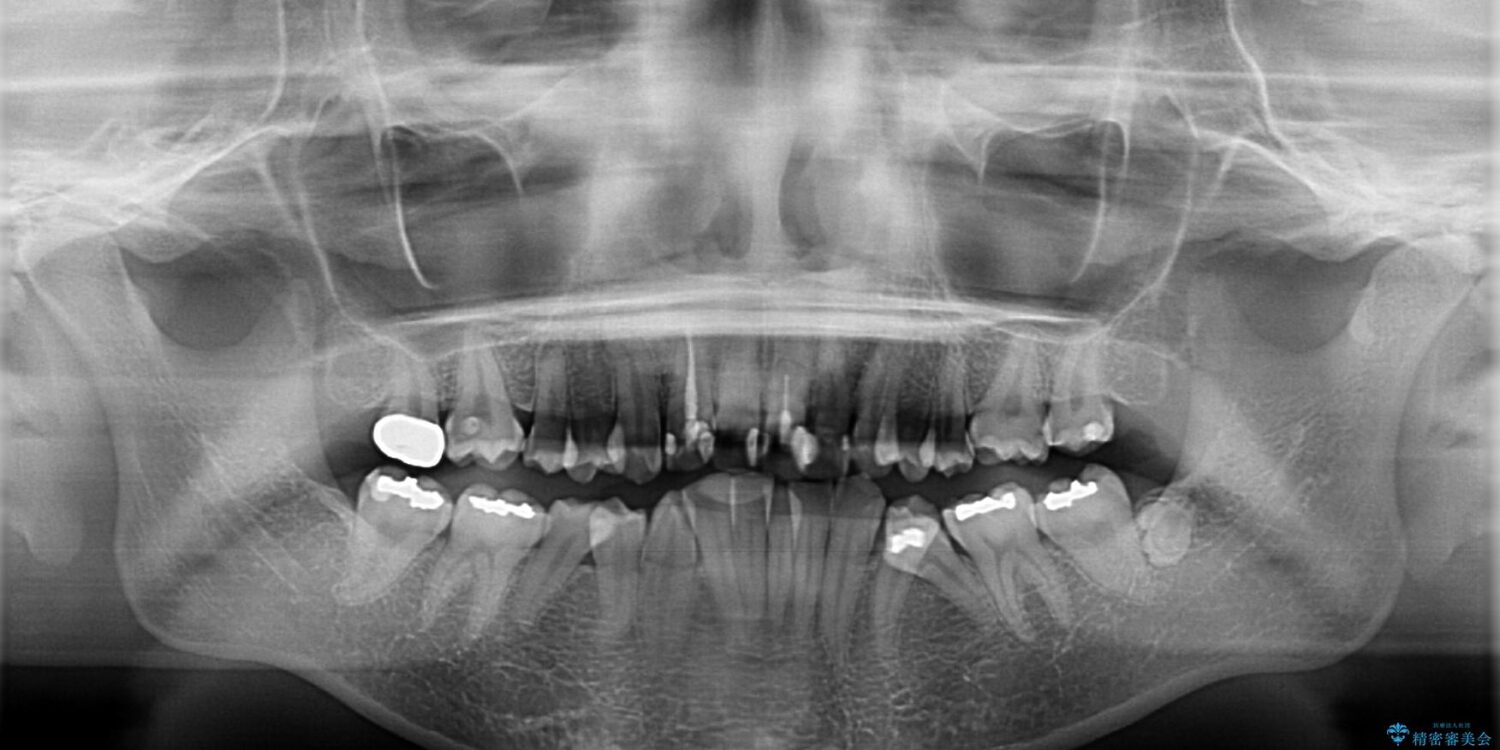

内側に倒れ込んだ歯や下の前歯が隠れてしまうほどの咬み合わせを改善したいとのことで来院された患者様です。

治療計画

下顎の叢生を解消するために抜歯が必要であり、奥歯の咬み合わせや口元の印象から、上顎も同様に抜歯と判断し、上下左右の第1小臼歯4本抜歯してワイヤー装置にて矯正治療を行うこととしました。

治療前

• デコボコと深い咬み合わせ ワイヤー装置での抜歯矯正 治療前画像